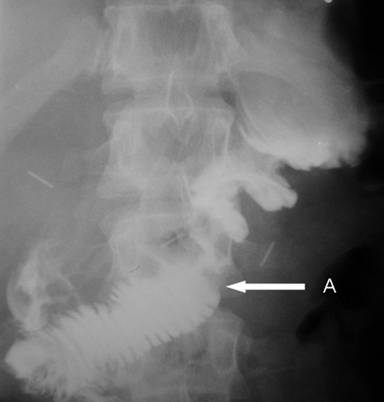

The postoperative course was uneventful. Cholangiography and a barium meal (Figure 5) on the 6th postoperative day revealed no leaks and good functioning of the neoduodenum and choledocho-pancreaticojejunostomy. The bile drain was removed 3 weeks later. Throughout the ensuing six-month follow-up, the patient had no complaints and gained 4 kg.

Figure 5. X-ray barium meal examination six days after the pancreas-preserving subtotal duodenectomy (Case #1). No leaks and good functioning of the doudenojejunostomy (arrow). |